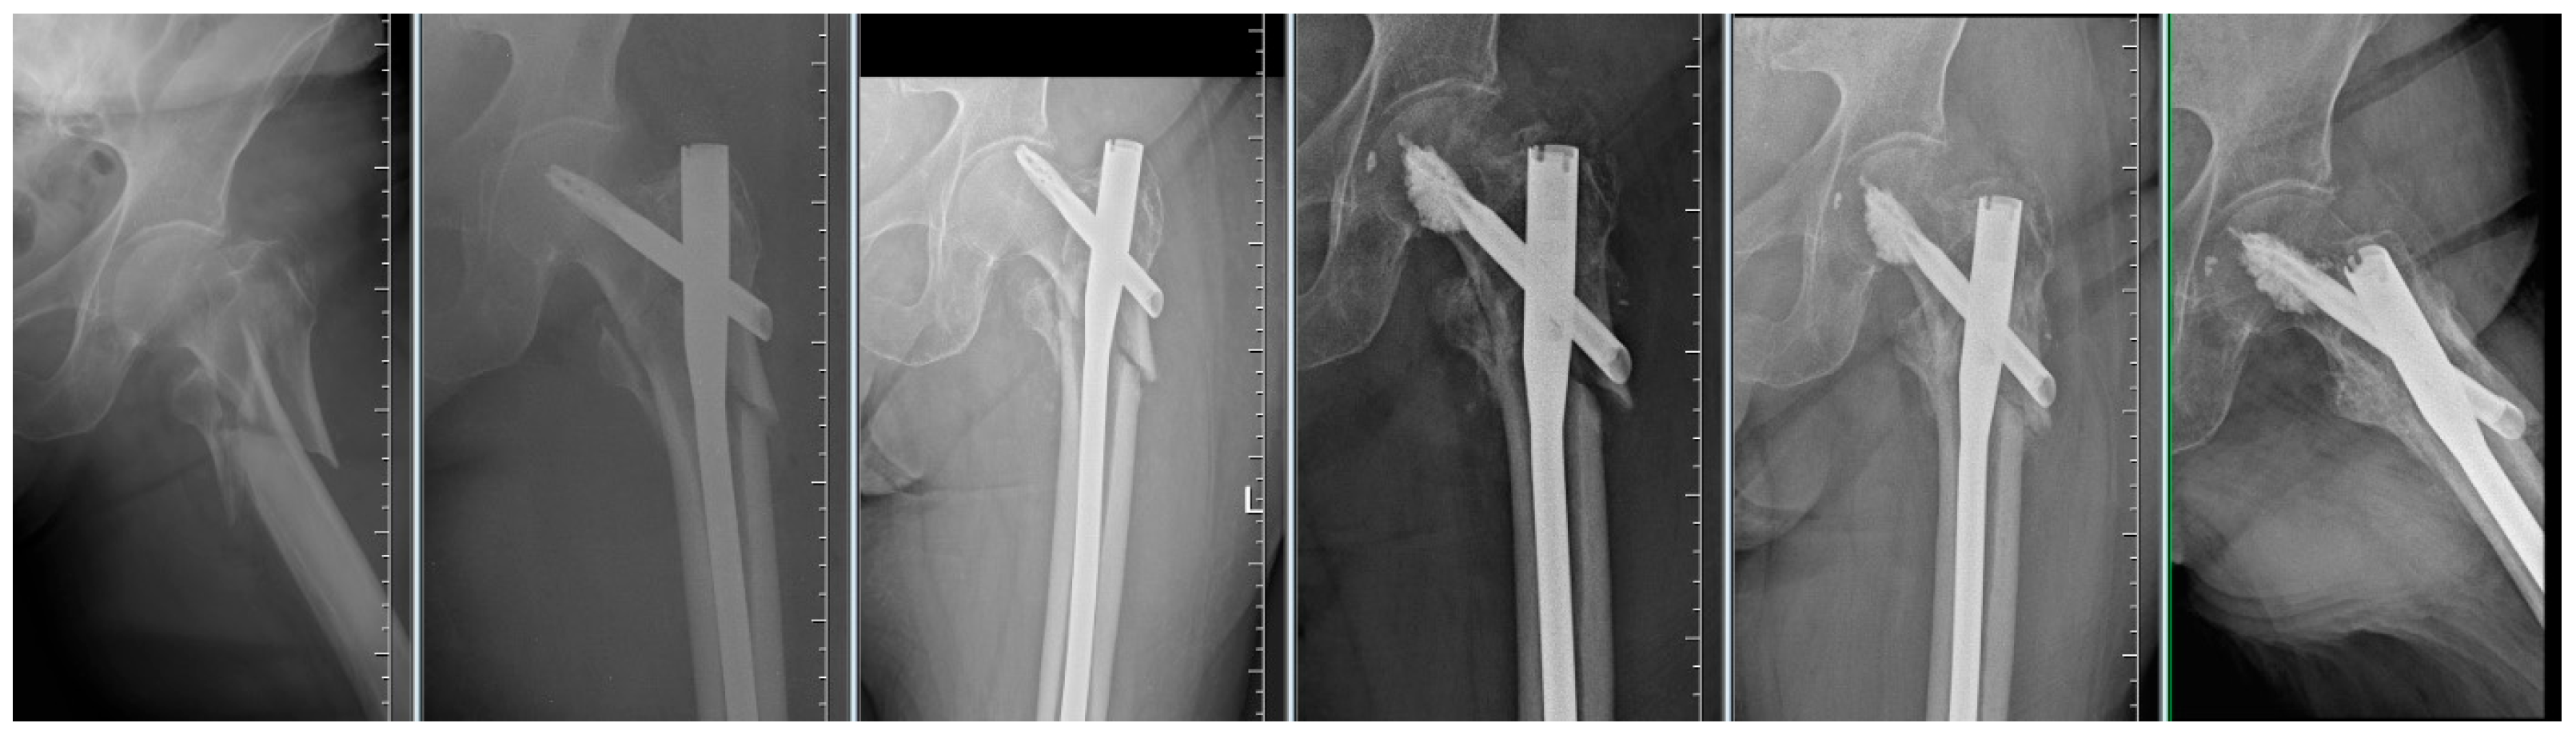

By evaluating the X-ray parameters, eight patients in the cohort in whom postoperative varus deformities of the femoral neck were greater than 10° were founded. Four patients did not have cement augmentation and four had cement augmentation of the nail. In three cases, the blade cut-out and, thus, failure of osteosynthesis was identified. In two women and one man with blade cut-out, a TFN-A implant without cement augmentation was implanted (Figure 3, Figure 4 and Figure 5). In these three cases, the medial cortical line and anterior cortical line were repositioned within 3 mm of dislocation at the anatomical interface. The blade cut-out in the group with cement augmentation was not observed.

Figure 4. Failure of osteosynthesis of a comminuted trochanteric fracture treated with TFNA. Reosteosynthesis was performed with cement augmentation of a new blade in the central–inferior position; image shows healed fracture.